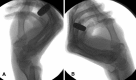

Methods: We addressed the morphology, load, and movement of the human thumb, emphasizing the CMC joint in normal and arthritic states. We present comparative anatomy, gross dissections, microscopic analysis, multimodal imaging, and live-subject kinematic studies to support or challenge the current understanding of the thumb CMC joint and its predisposition to disease.

Results: The current evidence suggests structural differences and loading characteristics predispose the thumb CMC to joint degeneration, especially related to volar or central wear. The patterns of degeneration, however, are not consistently identified, suggesting influences beyond inherent anatomy, repetitive load, and abnormal motion.